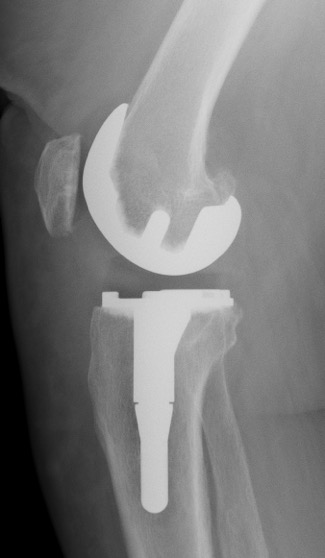

D. Prothèse à charnière (dernier recours si plus de ligament, reprises complexes, fractures sur prothèse)

Remplace les ligaments latéraux

charnière entre le fémur et le tibia (uniquement flexion et extension)

Quilles d’extension sont encore plus longues.